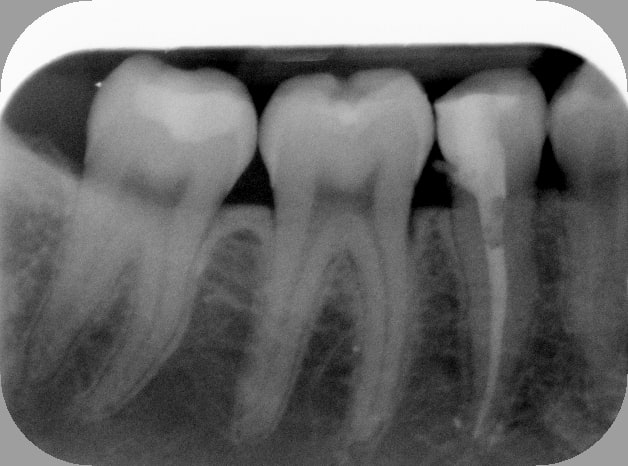

Putain de sa mère, j'ai pété un R25 à l'apex du 5°canal... Canal lingual en C, j'en étais au 8° canal pour l'instrument, j'aurai pas dû être joueur.

1h en comptant la dépose de la couronne, la RCR et la pro en bloc technique.

Avant t89ni5 - Eugenol

Apr s oqfrgc - Eugenol

Photo dentiste etgjzw - Eugenol